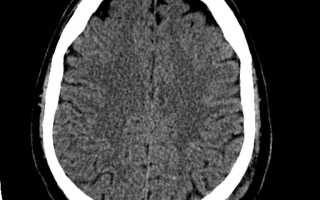

КТ при диффузном аксональном повреждении головного мозга показывает общее увеличение объёма мозга (вследствие его отёка и набухания), сужение или полное сдавление боковых и III желудочков, субарахноидальных конвексиальных пространств и цистерн основания мозга. На этом фоне могут быть выявлены мелкоочаговые геморрагии в белом веществе полушарий мозга, мозолистом теле, а также в подкорковых и стволовых структурах.

При развитии вегетативного состояния часто отмечается характерная динамика компьютерно-томографических данных: спустя 2— 3 нед. после травмы явления отека и набухания мозга регрессируют, мелкие очаги повышенной плотности (геморрагии) либо не визуализируются, либо плотность их становится пониженной, начинают отчетливо вырисовываться цистерны основания мозга, конвекситальные субарахноидальные щели, отмечается тенденция к расширению (ранее суженной) желудочковой системы. Обычно по времени это совпадает с переходом больных из комы в вегетативное состояние.

Данные компьютерной томографии на острой стадии ДАП характеризуются умеренным или сильным увеличением объема мозга, суживанием или сдавливанием боковых пространств и основания мозга. Плотность ткани чаще остается в норме, но может отмечаться ее снижение или повышение.

В белом веществе, мозолистом теле и стволовых отделах часто обнаруживаются мелкоочаговые скопления крови. Динамика компьютерной томографии у пациентов с ДАП характеризуется стремительным развитием симптомов дегенеративного процесса.

Через 3-4 недели после получения травмы выявляются сгустки спинномозговой жидкости в лобных областях и меж полушарий, которые могут исчезнуть по мере нормализации психоневрологического состояния.

Для компьютерной томограммы головного мозга при диффузном аксональном повреждении головного мозга характерно увеличение объема мозга вследствие его отека, набухания, гиперемии со сдавленней желудочков мозга и субарах-пондальных конвекситальных пространств. При этом часто выявляются мелкоочаговые геморрагии в белом веществе полушарий мозги, мозолистом теле, а также в подкорковых и стволовых структурах.